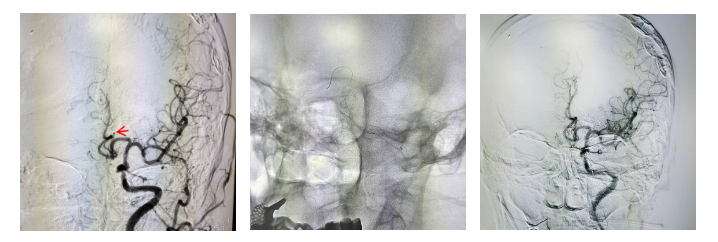

在与患者家属充分沟通病情并告知家属备选方案后,家属坚定选择积极治疗方案。神经介入团队刘彦伟副主任医师接到通知后,通知导管室进行术前准备,与刘哲主治医师共同为患者实施脑血管造影检查,精准锁定“肇事血管”——左侧大脑前动脉A1段完全闭塞。

考虑患者高龄,颅内血管严重迂曲,不适合动脉取栓,在征得家属同意后,介入团队迅速实施动脉溶栓治疗:微导管精准送至左侧颈内动脉终末段接近左侧大脑前动脉起始处,缓慢推注尿激酶20万单位。等待5分钟后,复查造影发现闭塞的左侧大脑前动脉再通,血流恢复通畅!此时患者意识逐渐清晰,从术前完全失语恢复到能简单交流,原本完全瘫痪的右侧肢体也可自主活动。